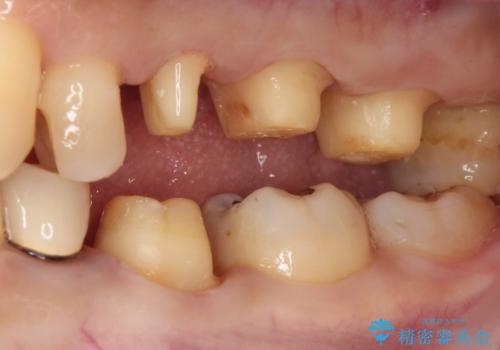

- 奥歯の銀歯をセラミックの白い歯にして、しみる症状も改善したいとのことで来院された患者様です。

知覚過敏の症状が強い歯と、銀歯の範囲や銀歯の下のむし歯が大きい歯は、インレー修復では対応が難しいためオールセラミッククラウンで、インレー修復で対応が可能な歯ではセラミックインレーにて修復することとしました。